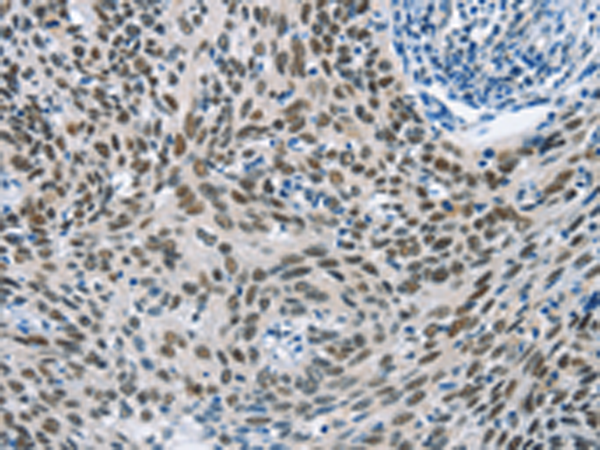

分类: 科研抗体货号: P11594别名: BAI2应用: IHC反应种属: Human, Mouse